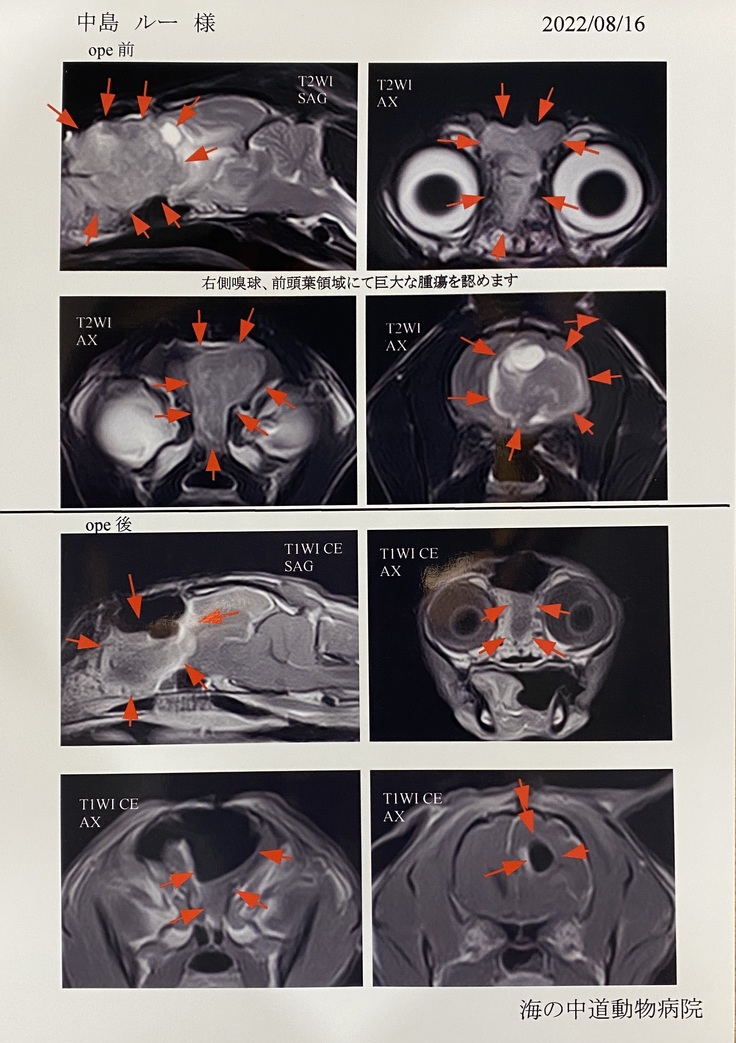

腫瘍は非常に大きく成長しており、鼻の少し奥の所から脳幹の部分まで広がっているとのことでした。それが原因で鼻が効かなくなり、ご飯もわからなくなっているのです。そして症状として食欲不振、旋回、体の麻痺が起きているのでした。

検査結果は前回より悪く、腫瘍もさらに大きくなっているとのことでした。腫瘍が脳を強く圧迫しており、脳の中心の溝もずれているとのことでした。 前回よりも視神経も圧迫しており、左目はほとんど見えていないのではないかとのことでした。今までにない発作も1、5倍くらいの腫瘍の大きさからくるものでした。

※病院より掲載の許可を得ています。